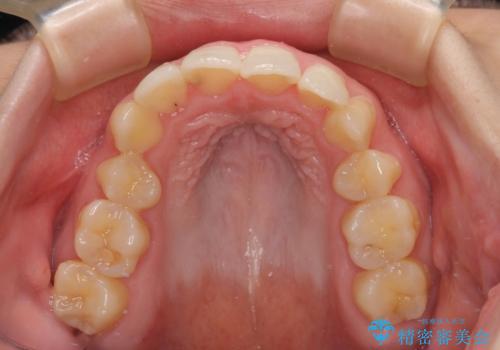

後戻りの再矯正 ワイヤー装置でデコボコと隙間を改善

- 学生時代の抜歯矯正の後戻りが気になり、再矯正を希望して来院された患者様です。

マウスピース矯正は継続する自信がなく、気になるところを短期間で改善したいとのことで、ワイヤー装置にて矯正治療を行うこととしました。

詰め物で隠していた下顎前歯の隙間は、歯軸を改善することで詰め物を除去しても隙間が目立たなくなりました。

まだ改善したいところはありましたが、患者様自身は大変満足されたとのことで、治療を終えることとなりました。